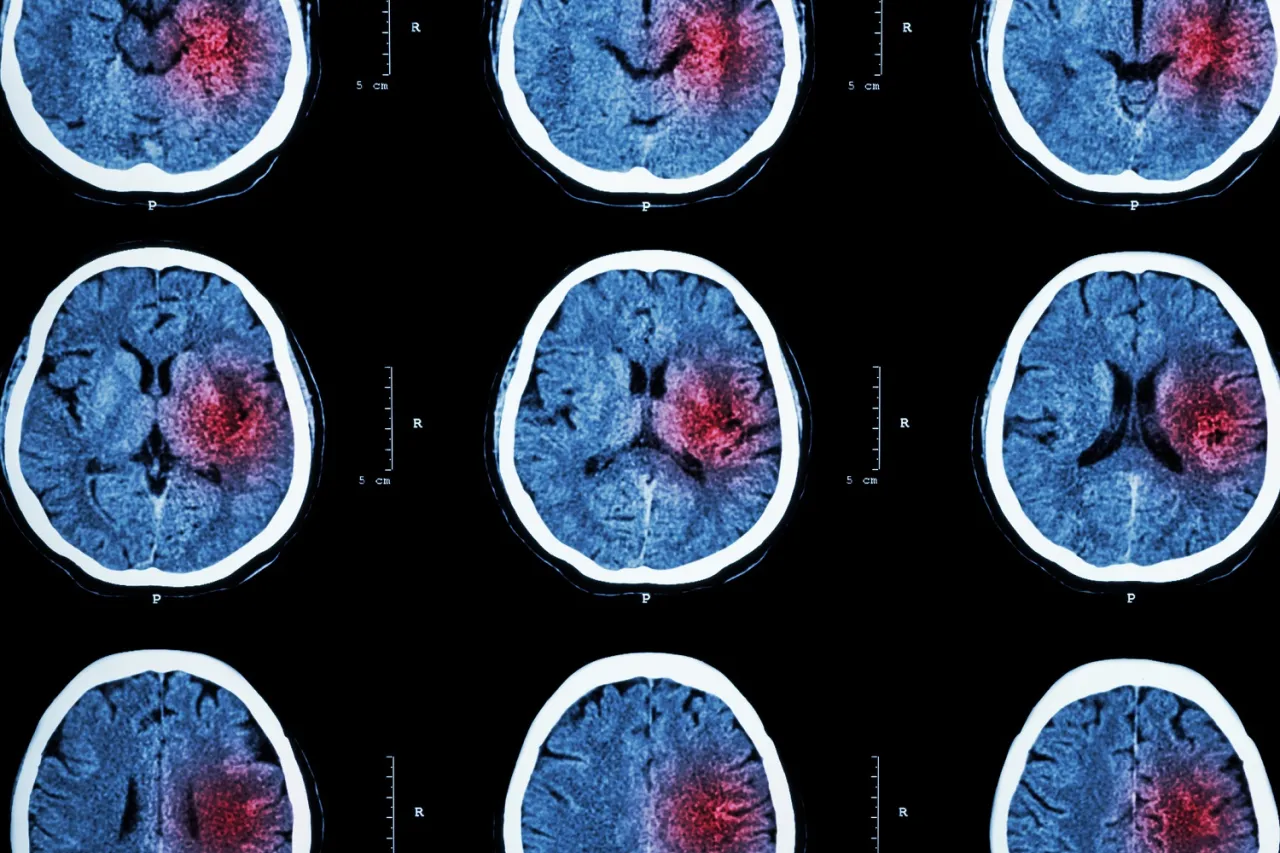

Udar krwotoczny (potocznie: wylew): gdy pęknięte naczynie zalewa mózg krwią (ok. 20% przypadków)

Ten typ udaru odpowiada za około 15-20% wszystkich przypadków. Jego mechanizm jest odwrotny do udaru niedokrwiennego: jest spowodowany pęknięciem ściany naczynia krwionośnego w mózgu. Krew wylewa się do tkanki mózgowej (krwotok śródmózgowy) lub do przestrzeni otaczającej mózg (krwotok podpajęczynówkowy). To właśnie ten typ udaru jest potocznie nazywany "wylewem". Główne przyczyny to: